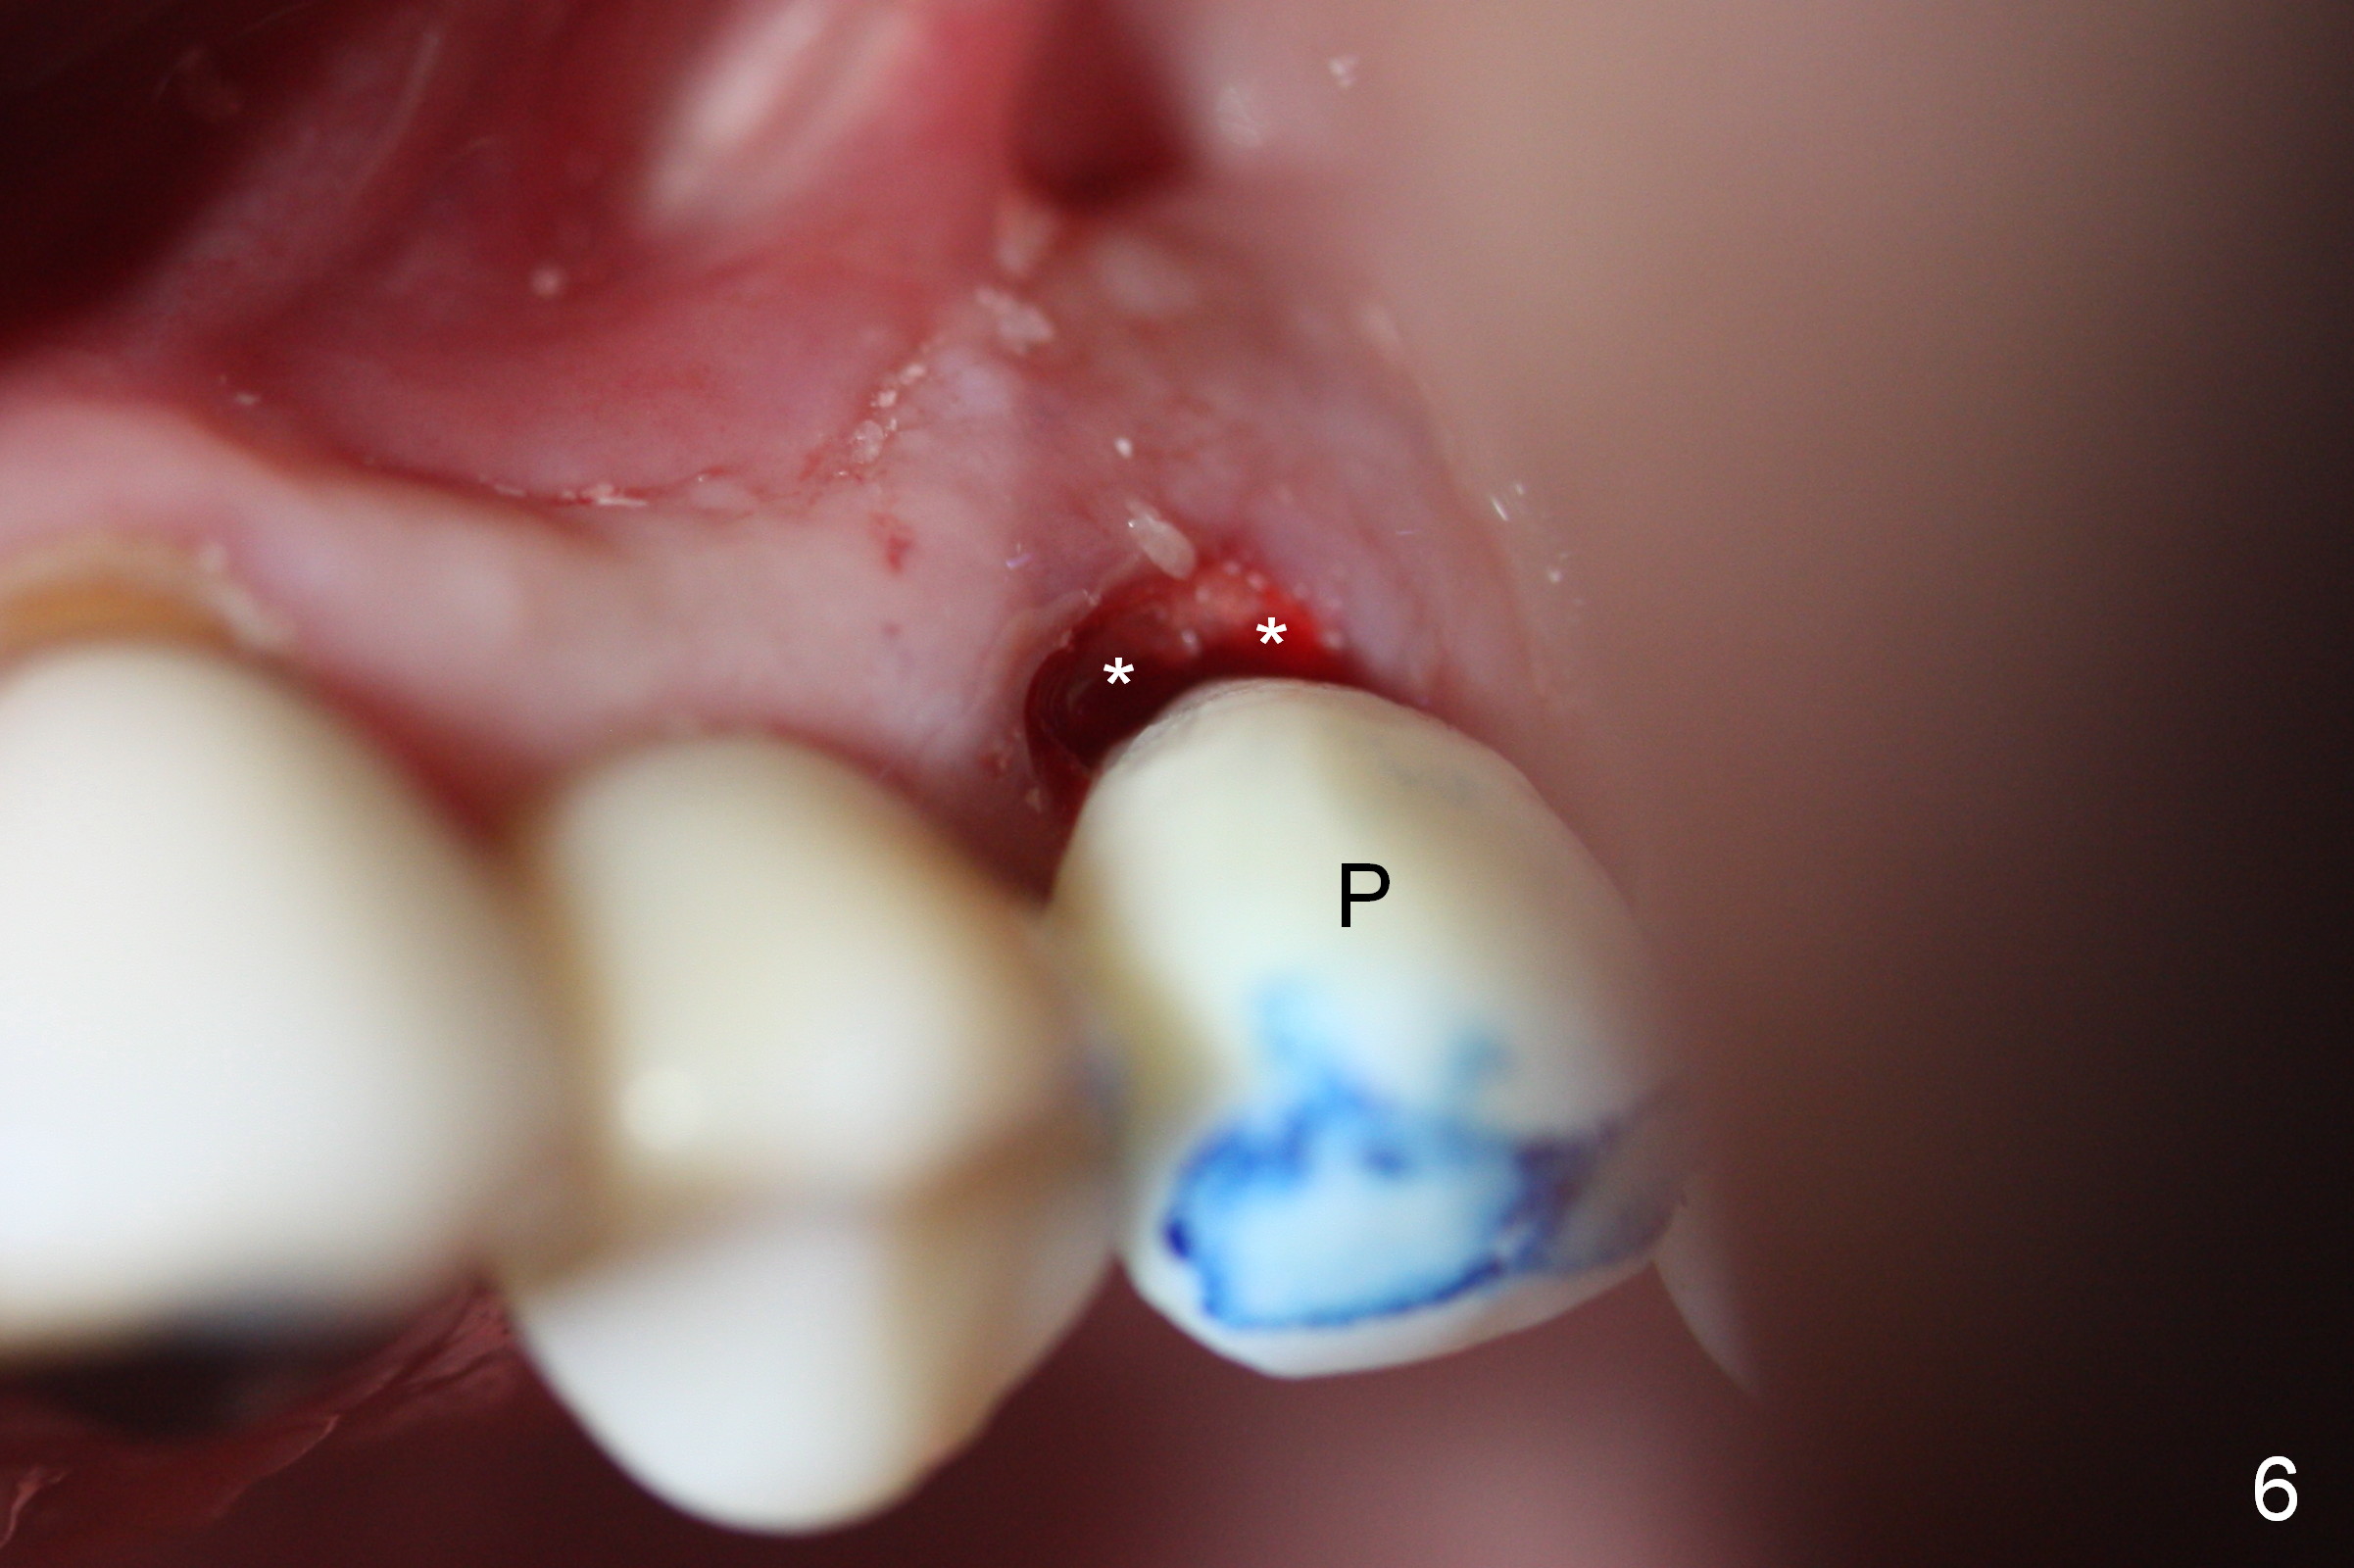

Extraction of the affected 2nd premolar is easy; the apical bone is so hard that drill and reamers have to be used for osteotomy, followed by insertion of a 4.5 mm tap with stability (Fig.1 T). The sinus floor (^) is lifted. There is no sign of sinus membrane perforation before placement of a 4.5x14 mm implant (Fig.2 I); sinus lift is performed (*: autogenous bone mixed with Mineralized Cancellous Human Allograft, Impladent); an immediate abutment (3.5x3 mm) is placed (A). With gauze placed in the buccal gap (Fig.3 G), the margin of the implant (I) is prepared for an immediate provisional fabrication. Mixture of autogenous bone (from reamers), allograft and Osteogen is placed in the remaining socket (Fig.4,5 *). When the relined (1st modification), trimmed and polished provisional is reseated (Fig.6 P), the bone graft (*) is not completely covered. New acrylic (2nd modification) is added to the margin of the provisional (Fig.7 *) for containment of the graft. There is almost no buccal plate; Osteotape (collagen membrane with Osteogen) is placed against the buccal wall of the socket prior to bone grafting. The remaining small pieces of the Osteotape (Fig.7 <) are laid over the bone graft before reseating the final provisional. With "complete socket seal", perio dressing is unnecessary.